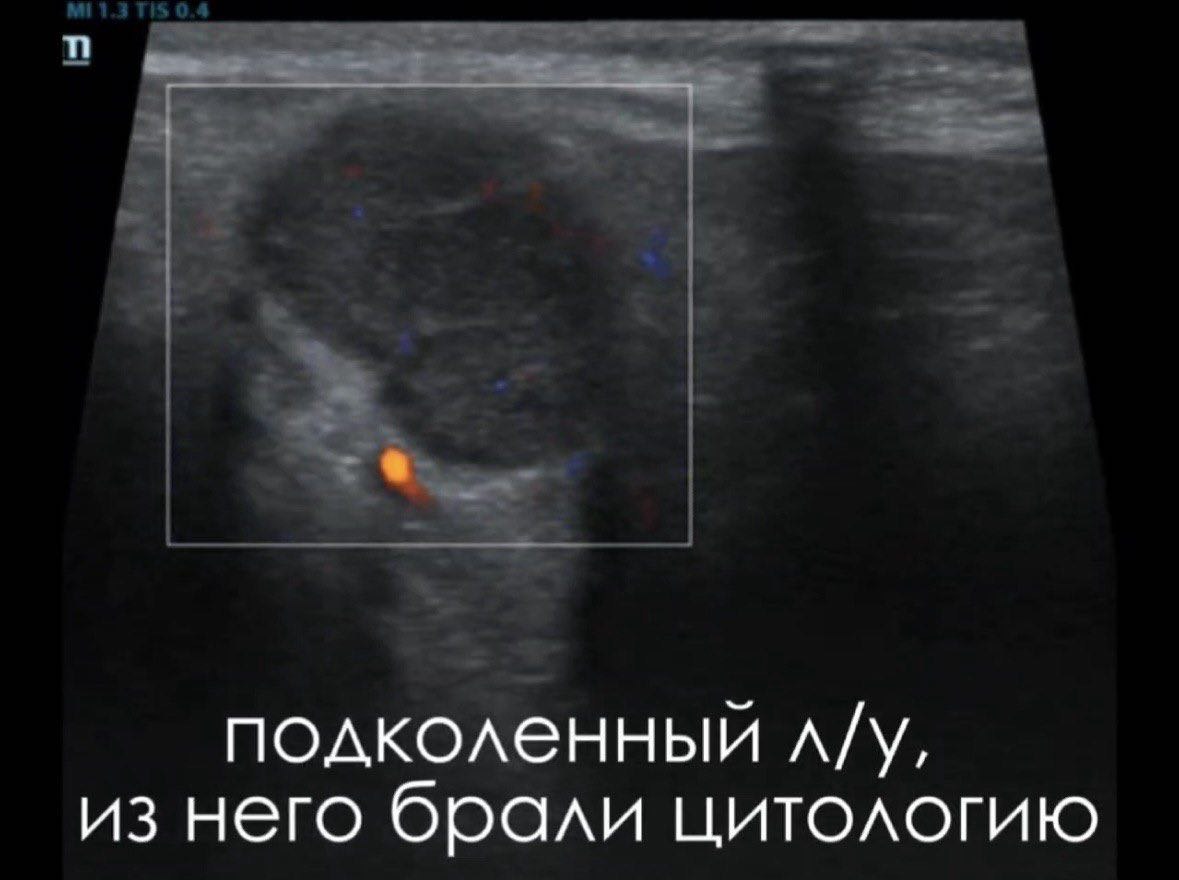

После исследования при беглом осмотре также было обнаружено увеличение поверхностных лимфатических узлов, в том числе подчелюстных, подколенных, паховых и других, а также их аналогичные структурные изменения на УЗИ. Владелец оперативно связался с лечащим врачом и обговорил проведение тонкоигольной биопсии для цитологической верификации лимфаденопатии. По согласованию с врачом и владельцем было принято решение взять биопсию из подколенного л/у - это достаточно эффективная тактика при мультицентрическом поражении лимфатических узлов, поскольку материал чаще всего достаточно информативен, а доступ гораздо проще и не требует седации даже у беспокойных пациентов.